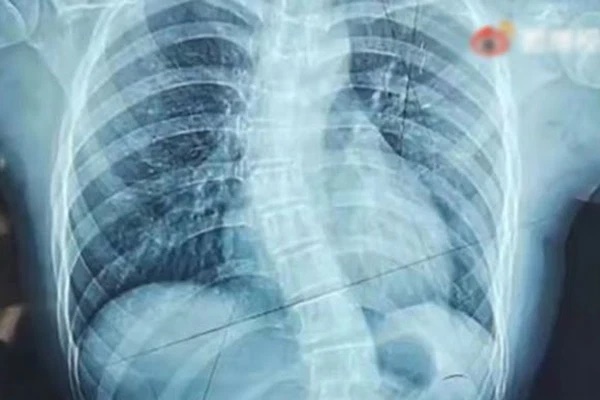

Chụp X-quang phát hiện Amy bị cong vẹo cột sống 15 độ hình chữ S. Chân trái dài hơn chân phải 1 chút, tay phải cũng ngắn hơn tay trái, vùng xương sườn và xương chậu biến dạng nhẹ.